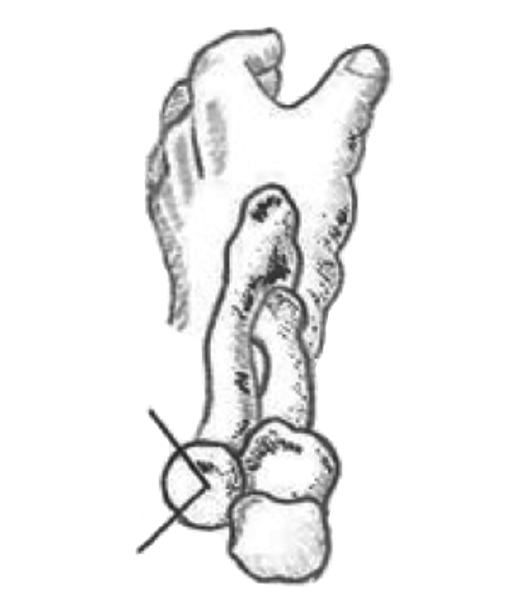

Figura 5. La “zona segura”, lugar donde se colocará una placa de bajo perfil en caso de precisar osteosíntesis si también existe afectación del cuello del radio.

- RAFI: la técnica se complica en presencia de más de 3 fragmentos o en fracturas del cuello del radio con pérdida completa del contacto cortical(14). Existen en el mercado placas de bajo perfil para sintetizar la cabeza al cuello. Para evitar bloquear la pronosupinación tendremos que colocarla en la llamada “zona segura”. Esta se localiza en el cuadrante posterolateral de la cabeza y la podremos identificar con el codo en flexión, el antebrazo en posición neutra y trasladando la visión, proximalmente, de la zona situada entre la estiloides radial y el tubérculo de Lister (Figura 5). A veces será necesario aporte de injerto autólogo al corregir la angulación, que tomaremos del olécranon o del epicóndilo lateral(15). También está descrita una técnica que usa 3 tornillos con una configuración en trípode y que al parecer proporciona la misma estabilidad que una placa(16). Si no podemos conseguir una osteosíntesis estable, que permita una movilización precoz, entonces es preferible la sustitución protésica.